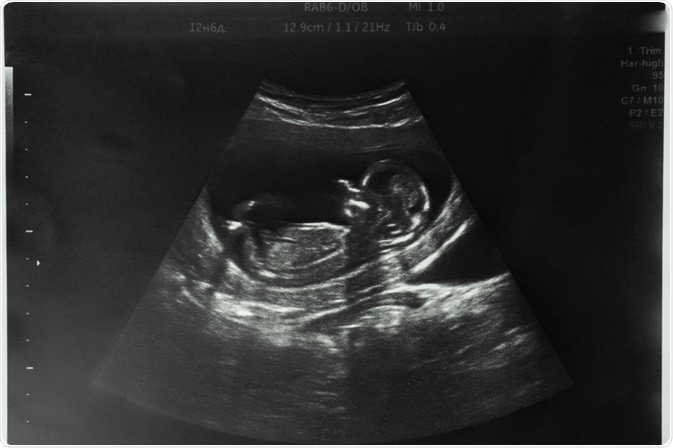

Fetus

Image Credit: SViktoria/Shutterstock.com

Ultrasound sex determination

High-resolution ultrasound now allows fetal morphology to be visualized clearly, thus paving the way for fetal sex determination at an earlier date during the first trimester. At an embryonic length (crown-rump length, CRL) of 76 mm or more, the chances of identifying the fetal sex accurately are 99% or more.